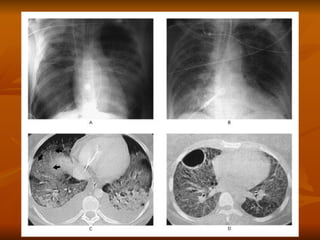

Critérios diagnósticos Início agudo Presença de condição predispondente Infiltrados bilaterais no R-x de tórax PaO2/FiO2 < 200 para SARA e < 300 para LPA Ausência de evidência de I.C Esq

Critérios diagnósticos Inícioagudo Presença de condição predispondente Infiltrados bilaterais no R-x de tórax PaO2/FiO2 < 200 para SARA e < 300 para LPA Ausência de evidência de I.C Esq